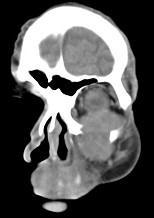

问题 男,65岁,左眼球突出近1年,鼻涕带血,面颊部隆起,同时面颊部有麻木感,CT检查如图,最可能诊断为()

选项 A.上颌窦息肉 B.上颌窦血管瘤 C.上颌窦囊肿 D.上颌窦癌 E.骨肉瘤

答案 D